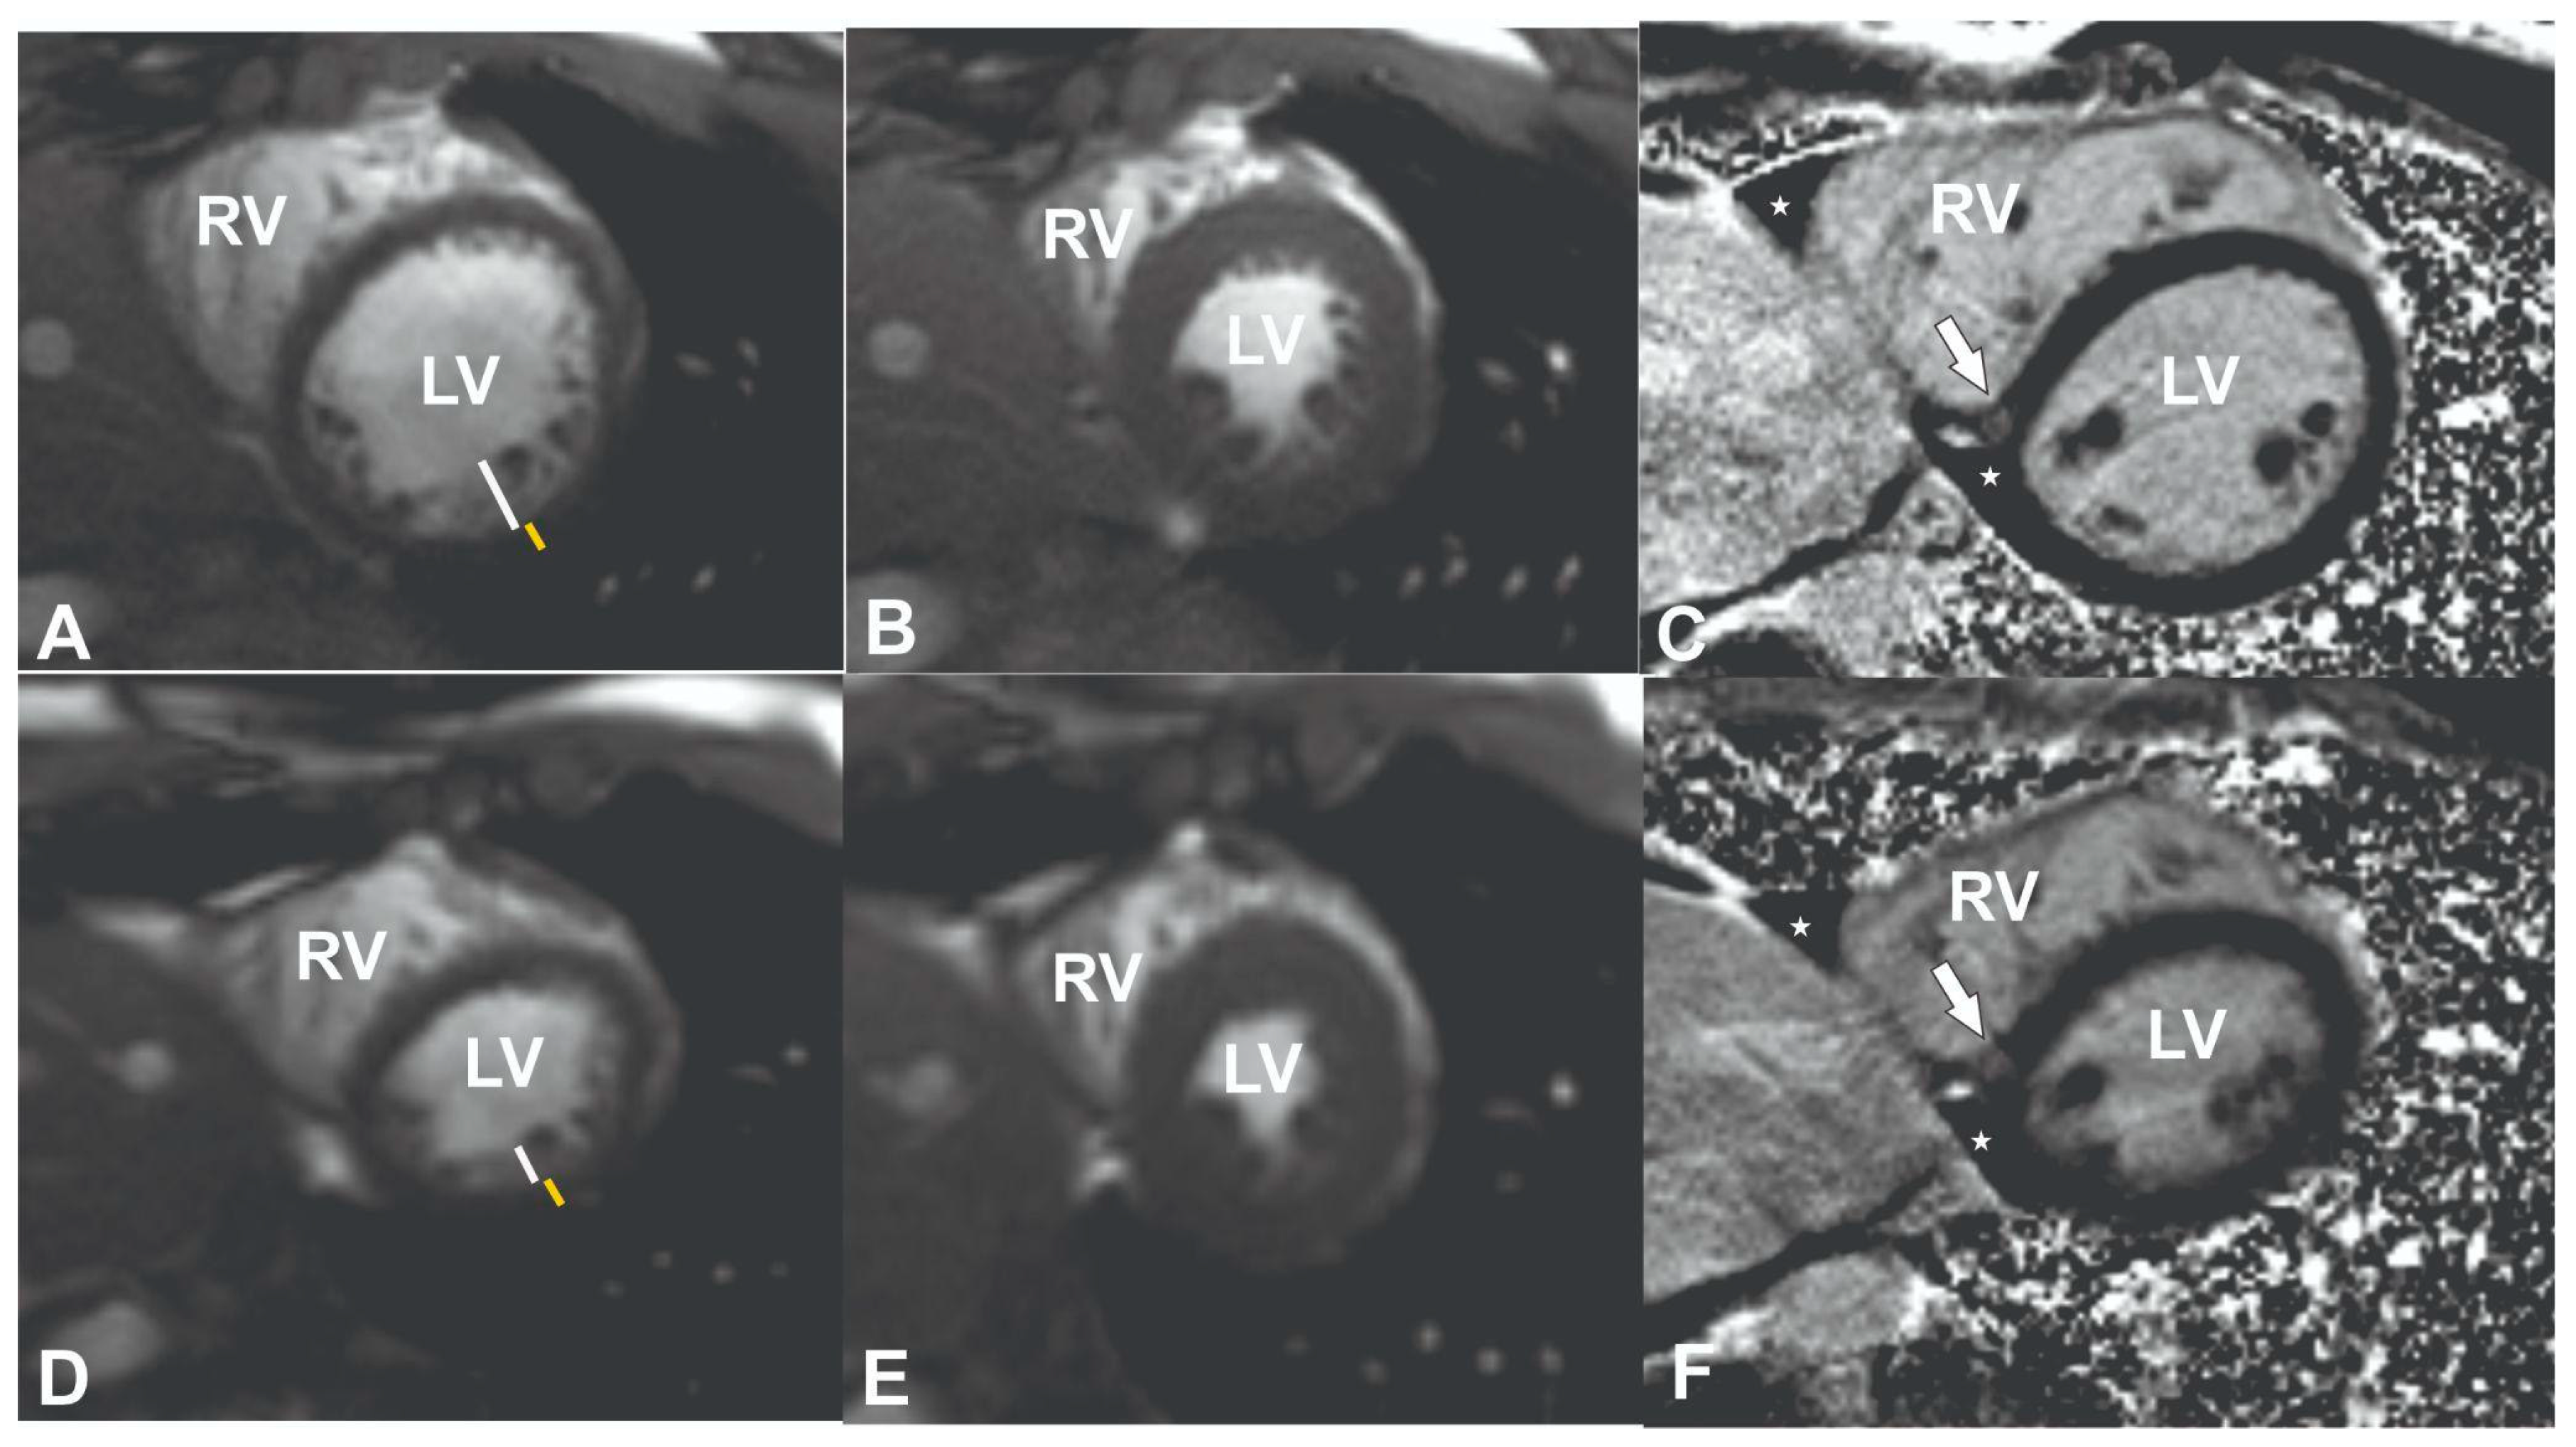

To exclude coronary artery pathology or anomalies, computed tomography angiography (CTA) was performed (Supplemental Video S4). No changes in the coronary vessels were found. Cardiac magnetic resonance (CMR) was performed to assess structural and functional cardiac changes and to exclude cardiomyopathies. The latter test showed slight LV dilatation (left ventricular end-diastolic volume index (EDVI) 104 mL/m2 (normal range <92), left ventricular end-systolic volume index (ESVI) 47 mL/m2 (normal range <30), borderline LV systolic function (55%, normal range >55%)) and signs of LV hypertrabeculation. The trabeculated to compacted myocardium ratio was up to 2.6 in end-diastole (Supplemental Videos S5–S7, Figure 1A–C). According to Petersen’s criteria, a normal ratio of trabeculated to compacted myocardium is <2.3 in end-diastole in long-axis heart views [15]. A non-specific focus of fibrosis was also detected on late gadolinium enhancement (LGE) images at the inferior left and right ventricle insertion points (Figure 1C, white arrow).

Figure 1.

CMR images of the patient at admission (A–C) and follow-up (D–F). Cine short-axis images at the midventricular level at diastole (A) and systole (B), representing left ventricular hypertrabeculation (its thickness is denoted with a white line and the compact myocardial layer with a yellow line), respective midventricular slice in inversion recovery sequence 10–15 min after contrast media injection (late gadolinium enhancement sequence, arrow pointing to the fibrotic focus at the inferior left and right ventricle insertion point, asterisk represents traces of fluid in the pericardial space at the inferior cardiac wall). Follow-up cine short-axis images at the midventricular level at diastole (A) and systole (B), representing the normalisation of left ventricular hypertrabeculation and a decrease in the left ventricle volumes after detraining. On a late gadolinium enhancement image, the same findings as in (C) were noticed.

After 2 years of detraining, the patient underwent a follow-up examination and additional CMR, which revealed the reverse remodelling of the LV with a decrease in left ventricular dilatation (EDVI from 104 to 97 mL/m2 (normal range < 92), ESVI from 47 to 40 mL/m2 (normal range < 30)); the LV ejection fraction at follow-up was within the normal range (58%) and the LV myocardium had a normal trabeculated to compacted myocardium ratio in diastole of 1.9 (normal range < 2.3) (Figure 1D–F, Supplemental Videos S8–S10). Additionally, a laboratory work-up showed a normal value of BNP < 10 ng/L with complete normalisation of transaminase and electrolytes. The patient reported no recurrence of syncopal episodes.

In this case, insertion point fibrosis was detected on lGE images at the inferior RV insertion point (Figure 1C, white arrow). RV insertion point fibrosis is frequently observed in athletes irrespective of age [29,30]. Its prevalence has been reported in 20–30% of athletes and is linked to the combination of the training load and intensity [31]. One hypothesis suggests that this pattern may result from pressure or volume overload in the right ventricle during intense exercise, causing micro-injuries that manifest as late gadolinium enhancement (LGE) [32]. In healthy elderly individuals, insertion point fibrosis may represent a normal ageing process and is often deemed an incidental finding when unaccompanied by other signs of cardiac damage [33]. Generally, it is considered to be benign in structurally normal hearts [34,35]. A similar LGE pattern has been observed in congenital heart disease patients with RV volume and pressure overload, in non-ischaemic dilated cardiomyopathy. The RV insertion LGE in the latter disease entities is associated with more advanced LV remodelling and a higher risk of clinical events [36,37].